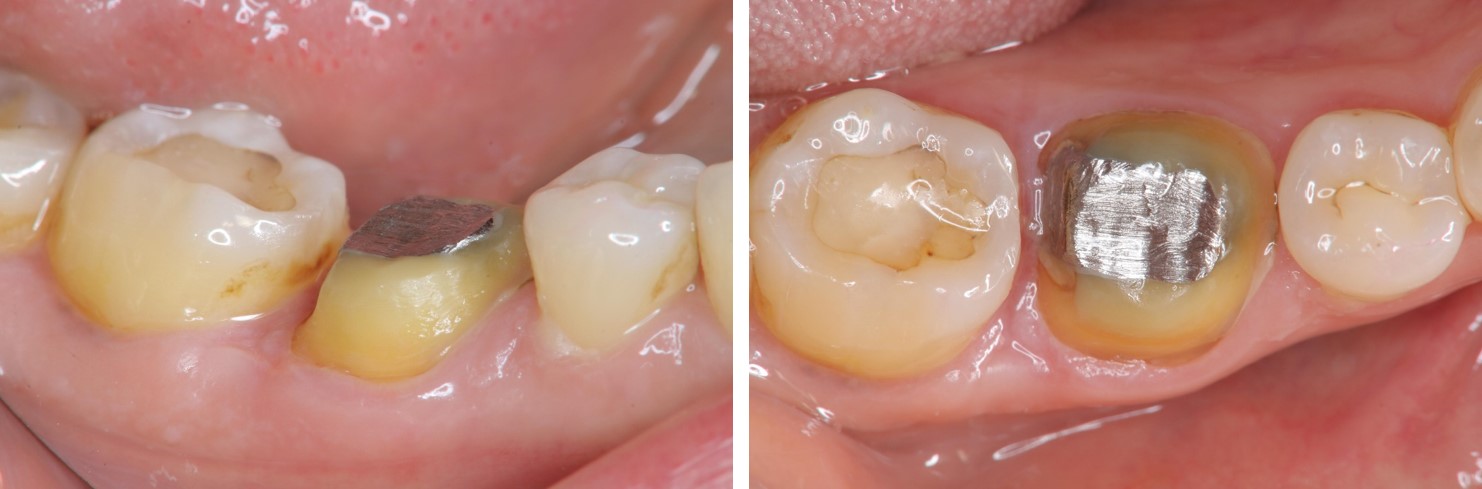

治療後,牙周咬合良好

治療後,密合度良好

術前、術後比較